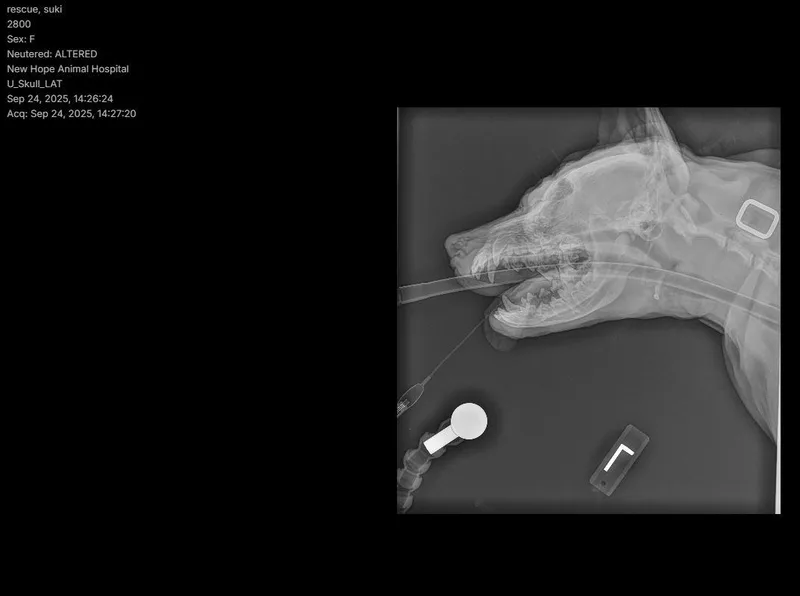

Suki has reached a wonderful milestone — she's feeling good, healing beautifully, and ready to find her forever home. After thorough veterinary care, it was discovered that Suki had suffered past head trauma that caused swelling, infection, and discomfort. Once a hidden bone fragment was removed, her body began to heal almost immediately — and the change has been remarkable. Today, Suki is brighter, more comfortable, happier, more playful, and clearly feeling like herself again. While she still has follow-up care and possible specialty treatment ahead, she's in a stable place and ready to move forward into a loving home where she can continue healing surrounded by care and consistency. Suki is a gentle, resilient girl with a calm spirit and a sweet heart. She's handled everything thrown her way with grace and trust, and she's ready for a new chapter filled with safety and love. **Suki is being fostered in Austin, TX. Paid transport can be arranged. Transport costs range from $200-400.** If you are interested in adopting, please complete an application @ https://form.jotform.us/41173109602142. Once approved, home visit and reference checks are also required. If you have further questions outside of this listing, please email chowmail.hccc@gmail.com.